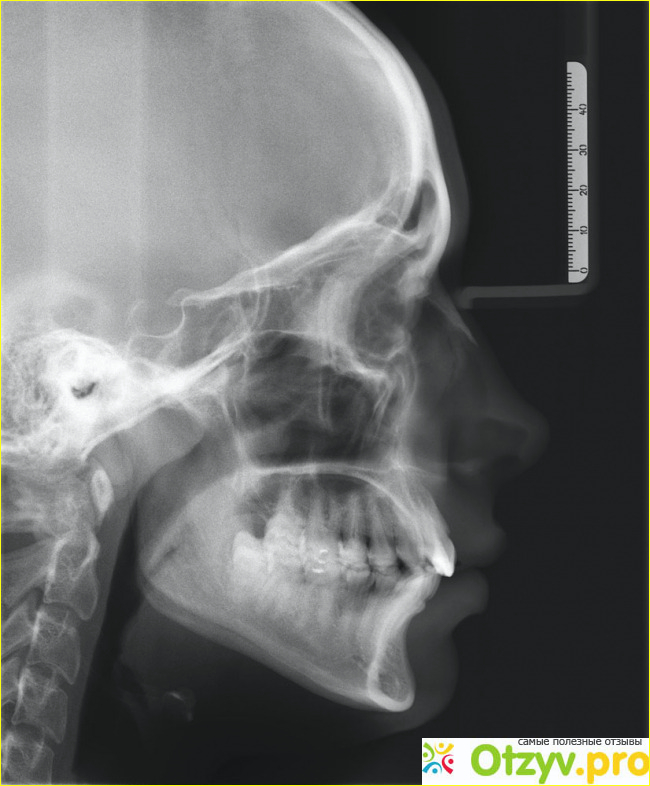

В тот день у нас был спаринг для областных соревнований и только трое лучших могли войти в сборную нашей области, поэтому страсти на ринге кипели. К сожалению мне не удалось войти в эту заветную тройку, потому что в четвертьфинале меня нокаутировал один из бойцов. В тот момент после одного удара я очень серьезно поплыл и упал на пол, бой решили остановить, кровь из носа хлестала ручьем, после чего мне закрыли дорогу на область, хотя я рассчитывал даже выиграть данный турнир. Но мои проблемы на этом не закончились. Я уже вроде как смирился с этим поражением и решил более менее привести себя в порядок, но все таки видок моего носа не позволял мне оставаться в хорошем виде, поэтому я решился на пластическую операцию, да я знал что это дорого и мне необходимо будет временно уйти из большого спорта. Но решение это мы приняли с женой. Так как на кону стояло или мой внешний вид или хорошая карьера, то мы решили сначала построить пункт номер один. А уже потом как все наладиться можно и вернуться в спорт. Дальше долго выбирали хирурга, который поможет исправить нам данную ситуацию. И нам посоветовали именно Сергея Николаевича Блохина, у которого очень хороший стаж работы и я полностью положился на него. Назначили нам операцию на определенную дату, к этому времени я полностью собрался духом и пришел в кабинет. Изначально он что-то рисовал на моем лице, видать что-то замерял, но делал это так больно. Я ему объяснял, почему нос искривился, он бы мог войти в положение и как то более аккуратно все делать. Но он стоял на своем и продолжал давить на нос. Тогда уже под анестезией сразу бы и делал. И вот наступил тот час, когда мне делали операцию. Я конечно же лежал в отключке, а жена очень переживала за кабинетом. Сама операция длилась порядка часу, после чего я отошел от анестезии, было жутко больно, наложены швы, состояние просто ужасное, везде кровища. Но я уж подумал что все прошло удачно, но как только моей жене разрешили зайти ко мне она ужаснулась, сказав, что нос весь какой то непонятный. Потом я присмотрелся в зеркало и заметил, как неудачно были наложены швы. И я был прав, буквально через пару минут кровь как хлынула, мне только и успели сделать повторную анестезию и я опять отключился.

Уж на второй раз все прошло куда более удачно, но сама операция была очень тяжелой и долгой. А все это из за того, что наш излюбленный квалифицированный пластический хирург неправильно наложил швы на носу. Поэтому пришлось делать двойную работу. Конечно же после того, как я пришел в себя, я все это ему высказал. Так как всю боль терпел еще до вскрытия, а потом еще так неаккуратно. Я полностью загадил кабинет кровищей, потерял ее достаточно. И в этом собственно вся их вина. Поэтому крайне настоятельно рекомендую не оперироваться у данного хирурга. Просто отвратительное качество работы. Вот прошло время, все вроде бы заживает, но я еще пока не думаю возвращаться обратно в большой спорт. Лучше пока позабочусь немного о себе, потому что во время поединков, ты об этом никогда не вспоминаешь. Через годик там может быть начну. После этой операции я пожаловался главврачу на этого хирурга. Надеюсь, что он в настоящее время больше не работает на своем месте. Всем спасибо за внимание и главное здоровья вам и вашим близким!